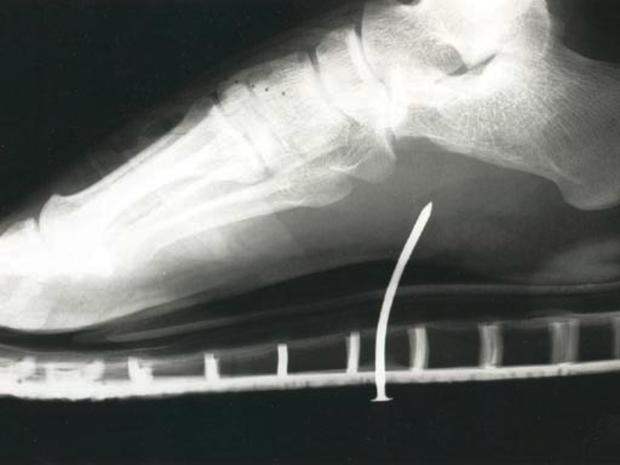

Watch your step

This young man stepped on a nail while wearing sandals.